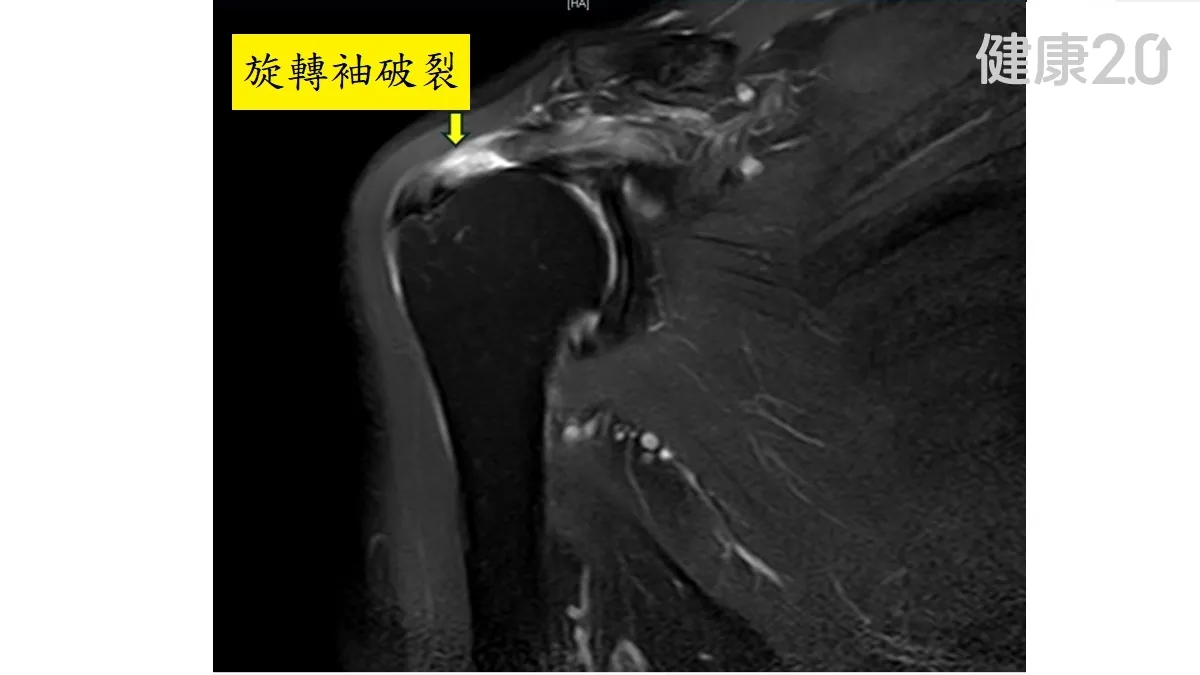

手舉不起來竟不是五十肩!肌腱破裂不手術 再復健還是痛

60歲的林女士最近發現手臂舉不起來,還以為是五十肩,就醫檢查才發現是肩膀的「旋轉袖」肌腱破裂。骨科醫師提醒,旋轉袖肌腱斷